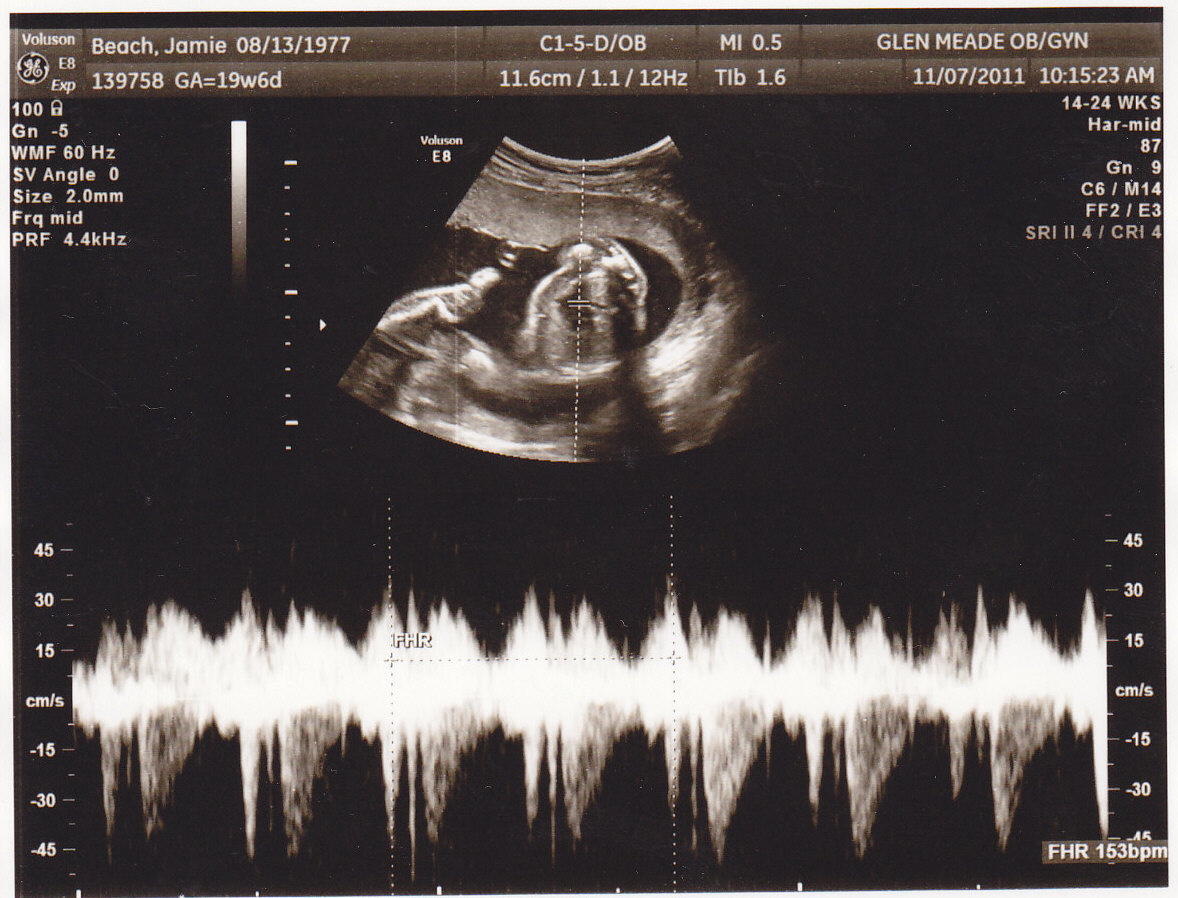

Baby's heartbeat is getting stronger and can be heard using a good old-fashioned stethoscope. Ask for a listen at your next prenatal visit! By 21 weeks, fetal bone marrow starts making blood cells—previously done by the liver and spleen. This may not sound that exciting, but it's good news.

Your baby now weighs about three-quarters of a pound and is approximately 10 1/2 inches long — the length of a carrot. You may soon feel like she's practicing martial arts as her initial fluttering movements turn into full-fledged kicks and nudges. You may also discover a pattern to her activity as you get to know her better. In other developments, your baby's eyebrows and lids are present now, and if you're having a girl, her vagina has begun to form as well.